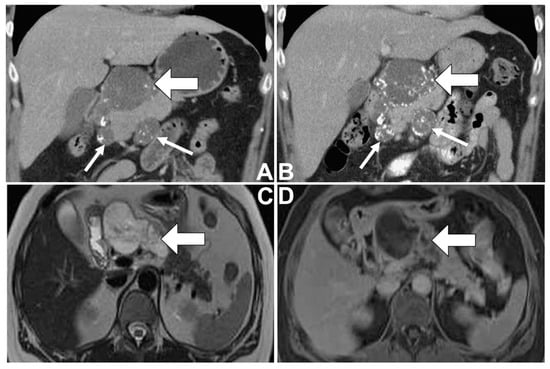

| Radiological | Location | Head (70%) | Body and tail (95%) | Head/head |

| Shape | Ovoid | Spheroid | Lobulated/lobulated | |

| Duct communication | Common | No | No/No | |

| Calcification | Some (20%) | Some (30%) (peripheral) | Some/Yes (internal and peripheral) | |

| MRI T2 high signal intensity | Yes | Yes | Yes/Yes (salt-and-pepper appearance) | |